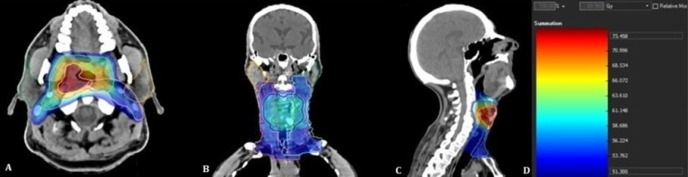

目的:探讨放疗(RT)后放疗剂量、18f -氟脱氧葡萄糖正电子发射断层扫描/计算机断层扫描(18F-FDG PET/CT)评估的唾液腺代谢变化与头颈癌患者口干严重程度的关系。方法:回顾性分析107例接受调强放疗或调容弧线治疗的头颈部恶性肿瘤患者。在治疗后PET/CT检查时评估临床口干严重程度。从治疗方案中提取平均腺体剂量和剂量-体积参数(V10-V50)。通过治疗前后PET/CT扫描的Δmaximum标准化摄取值和Δmean标准化摄取值评估代谢变化。研究了临床、剂量学和代谢变量之间的关系。结果:63.6%的患者出现中重度口干。较高的T和N分期与更严重的口干严重程度显著相关(pΔSUV值与平均剂量和剂量-体积参数显著相关,特别是在左腮腺,接受bbb30 Gy的患者代谢下降明显更大。腮腺比下颌骨腺表现出更强的剂量依赖性代谢变化,这与它们更高的放射敏感性一致。结论:尽管采用了先进的放射治疗技术,但口干仍然是一种常见的毒性。18F-FDG PET/CT可靠地捕获剂量依赖性唾液腺损伤,并反映肿瘤负荷对毒性风险的影响。这些发现强调了pet衍生的生物标志物作为预测常规剂量学参数之外的唾液功能障碍的综合工具的补充作用。

Methods: We retrospectively analyzed 107 patients treated with intensity-modulated RT or volumetric modulated arc therapy for head and neck malignancies. Clinical xerostomia severity was evaluated at the time of post-treatment PET/CT. Mean gland doses and dose-volume parameters (V10-V50) were extracted from treatment plans. Metabolic changes were evaluated by Δmaximum standardized uptake value and Δmean standardized uptake value between pre and post treatment PET/CT scans. The relationships between clinical, dosimetric, and metabolic variables were examined.

Results: Moderate-to-severe xerostomia occurred in 63.6% of patients. Both higher T and N stage were significantly associated with greater xerostomia severity (p<0.05). Patients with nodal metastases on pretreatment PET/CT demonstrated a higher prevalence of xerostomia. Dose-volume parameters (V10-V30 for parotids, V50 for submandibular glands) were significantly correlated with symptom severity. ΔSUV values were significantly associated with both mean dose and dose-volume parameters, particularly in the left parotid gland, where patients receiving >30 Gy showed markedly greater metabolic decline. Parotid glands demonstrated stronger dose-dependent metabolic changes compared with submandibular glands, consistent with their higher radiosensitivity.